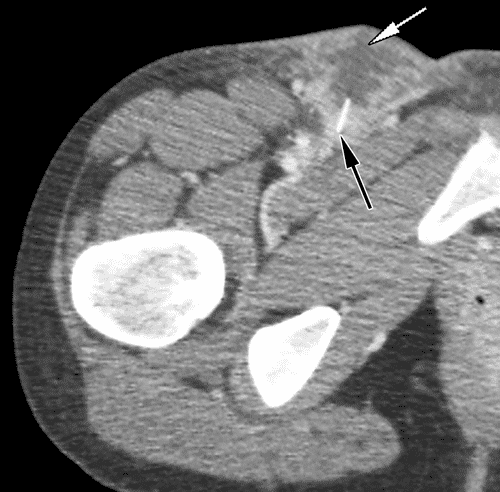

4.2. CT Scanner

Hình ảnh ổ giảm đậm độ trong mô mềm dưới da, bờ không đều, ngấm thuốc viền, và thâm nhiễm mỡ xung quanh.

Hình 3. Áp xe dưới da ở bệnh nhân nam 25 tuổi bị đau ở háng và sốt sau khi tiêm thuốc vào háng. Hình ảnh CT có tiêm thuốc cản quang: bẹn phải có ổ tụ dịch với thành dày ngấm thuốc (mũi tên trắng), phù hợp với ổ áp xe. Mô mềm dưới da xung quanh ổ tụ dịch sưng nề và ngấm thuốc, phù hợp với viêm mô tế bào. Lưu ý phần mỡ dưới da còn tương đối nguyên vẹn ở đùi bên và đùi sau để so sánh. Một mảnh kim bị gãy (mũi tên đen) được nhìn thấy sâu trong ổ tụ dịch.